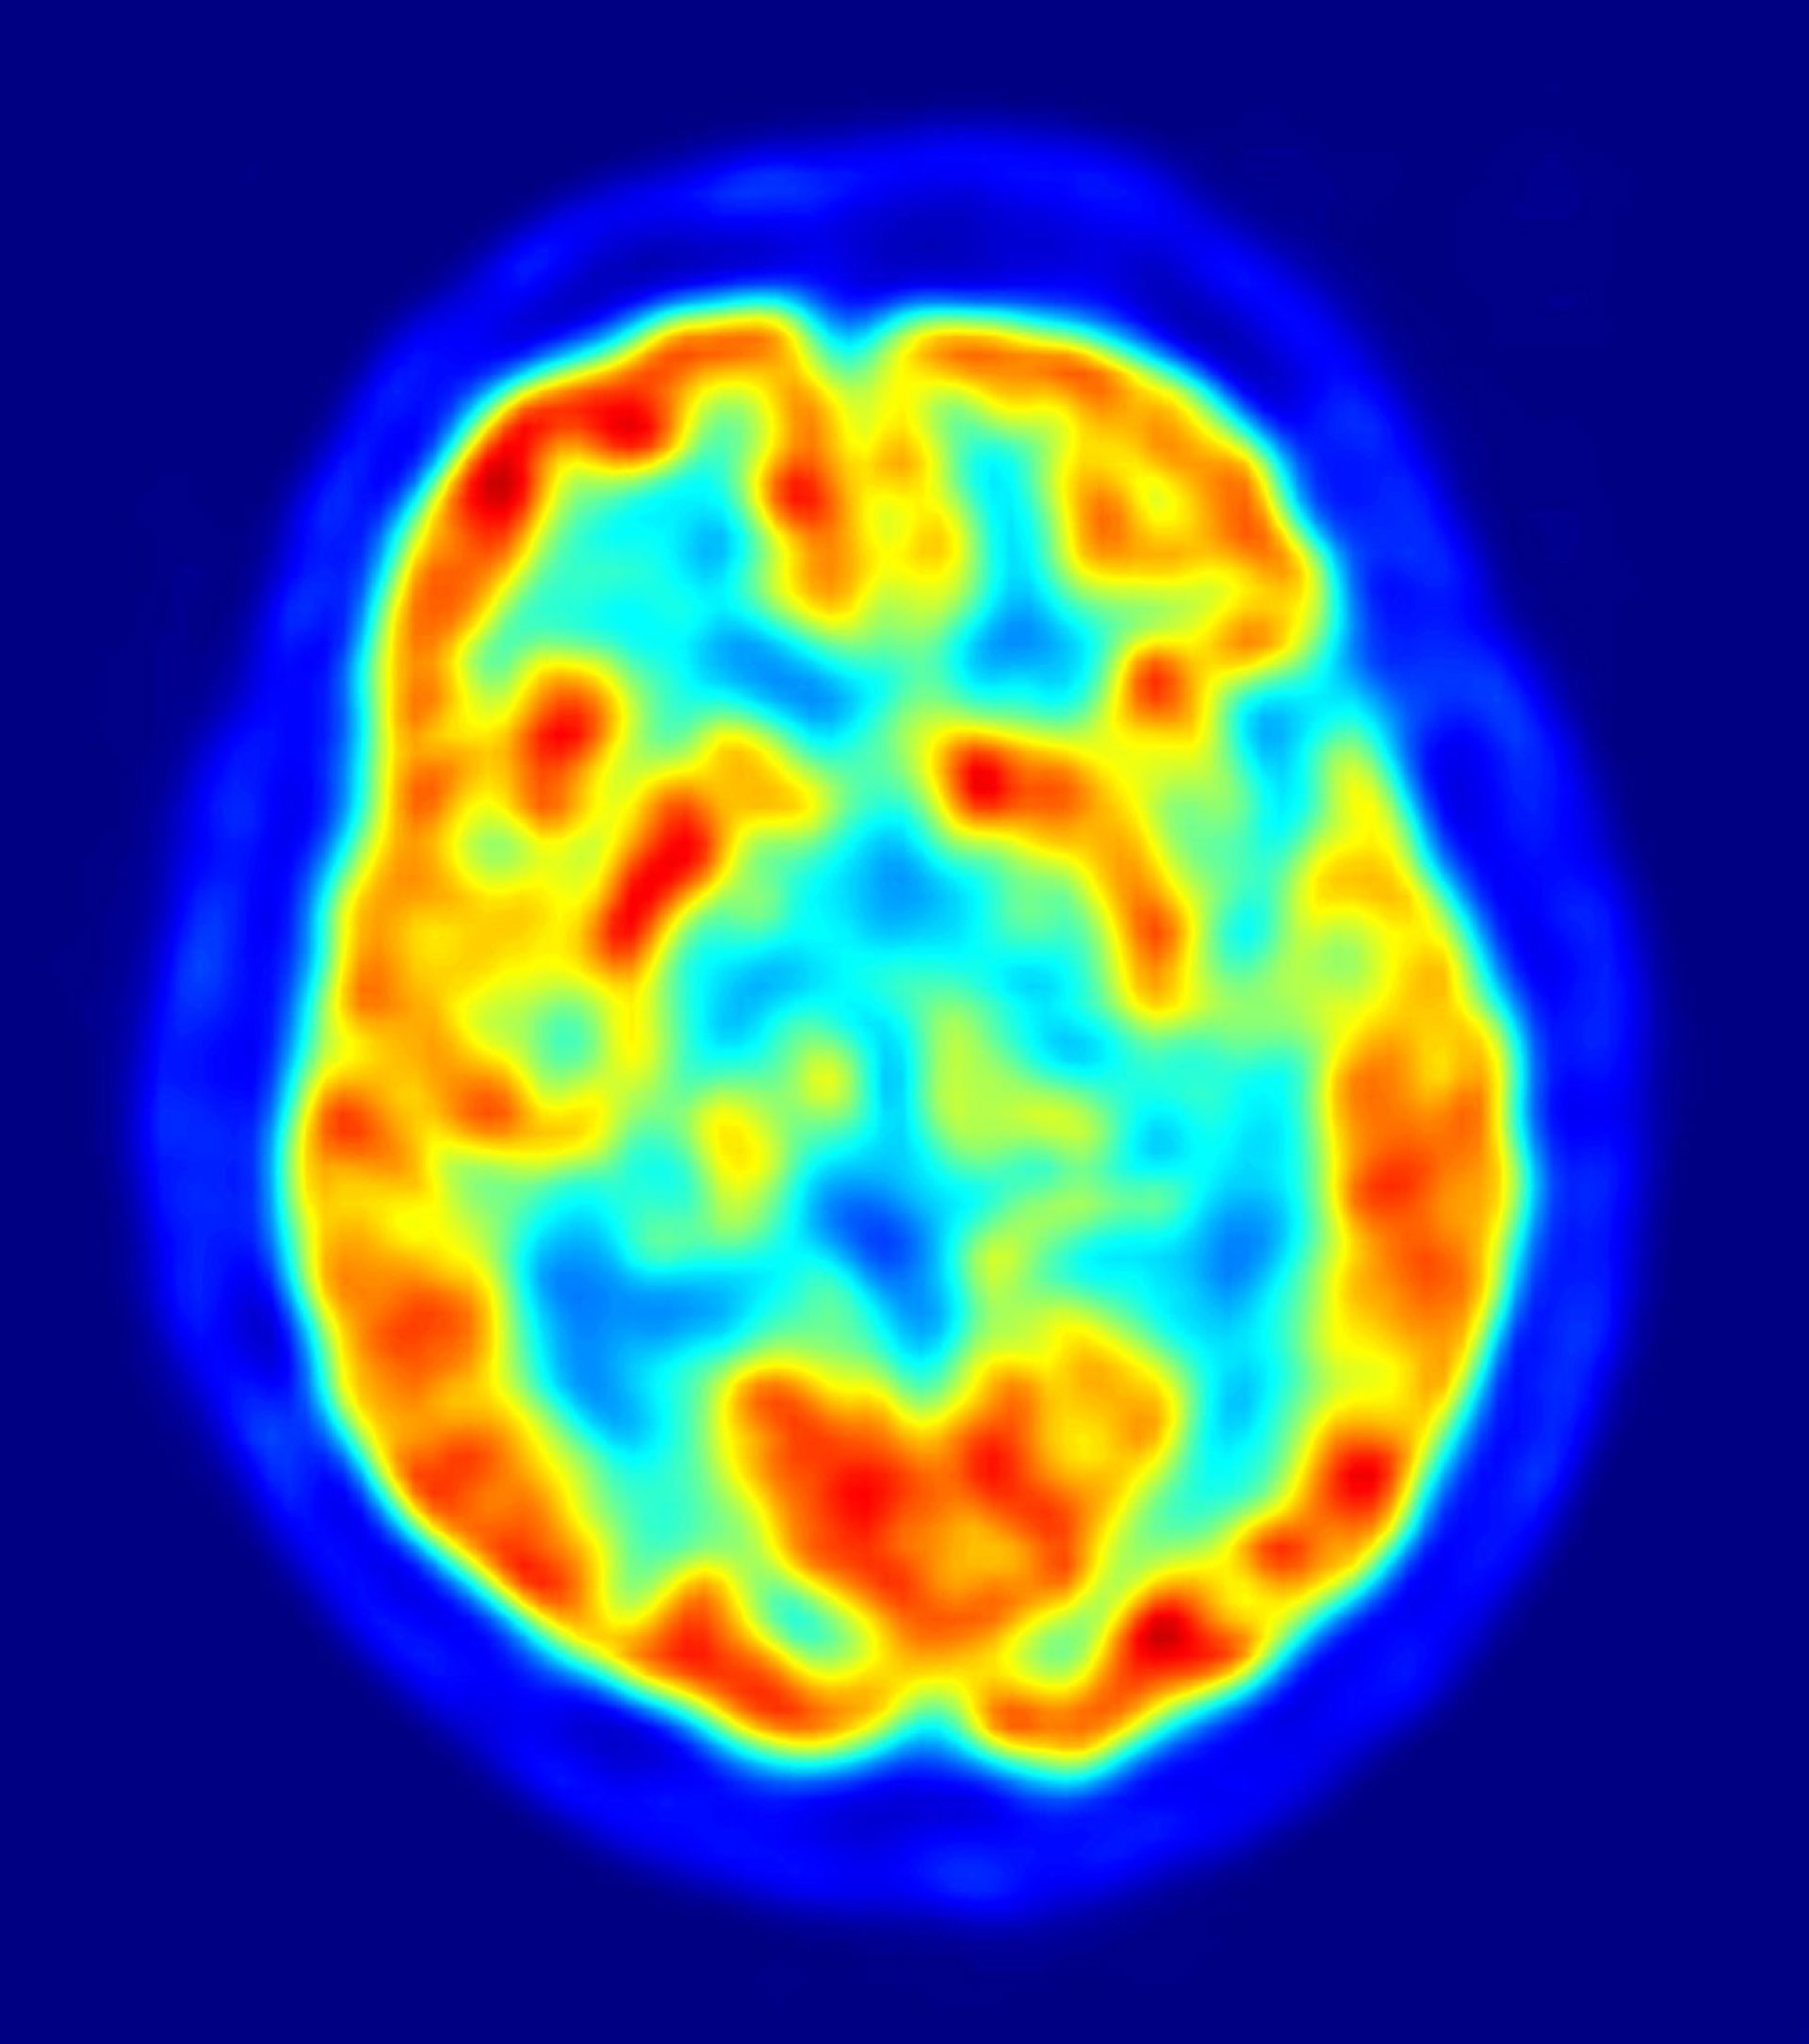

Rauschecker y DeWitt analizaron la literatura científica de estudios que investigan la percepción auditiva del habla en los seres humanos con diferentes métodos de exploración - ya sea a partir de la resonancia magnética funcional (fMRI) o a partir de tomografía por emisión de positrones (PET).

Los científicos encontraron 115 estudios de imágenes cerebrales de la percepción del habla, que en total incluyen a más de 1.900 participantes, y más de 800 coordenadas cerebrales para el procesamiento del habla. A continuación, utilizaron un tipo de análisis que les permitió medir el grado de acuerdo entre las coordenadas del cerebro de estos estudios.

Los resultados señalan la ubicación de la zona de Wernicke que en el lóbulo temporal izquierdo, en concreto, en la circunvolución temporal superior, frente a la corteza auditiva primaria.